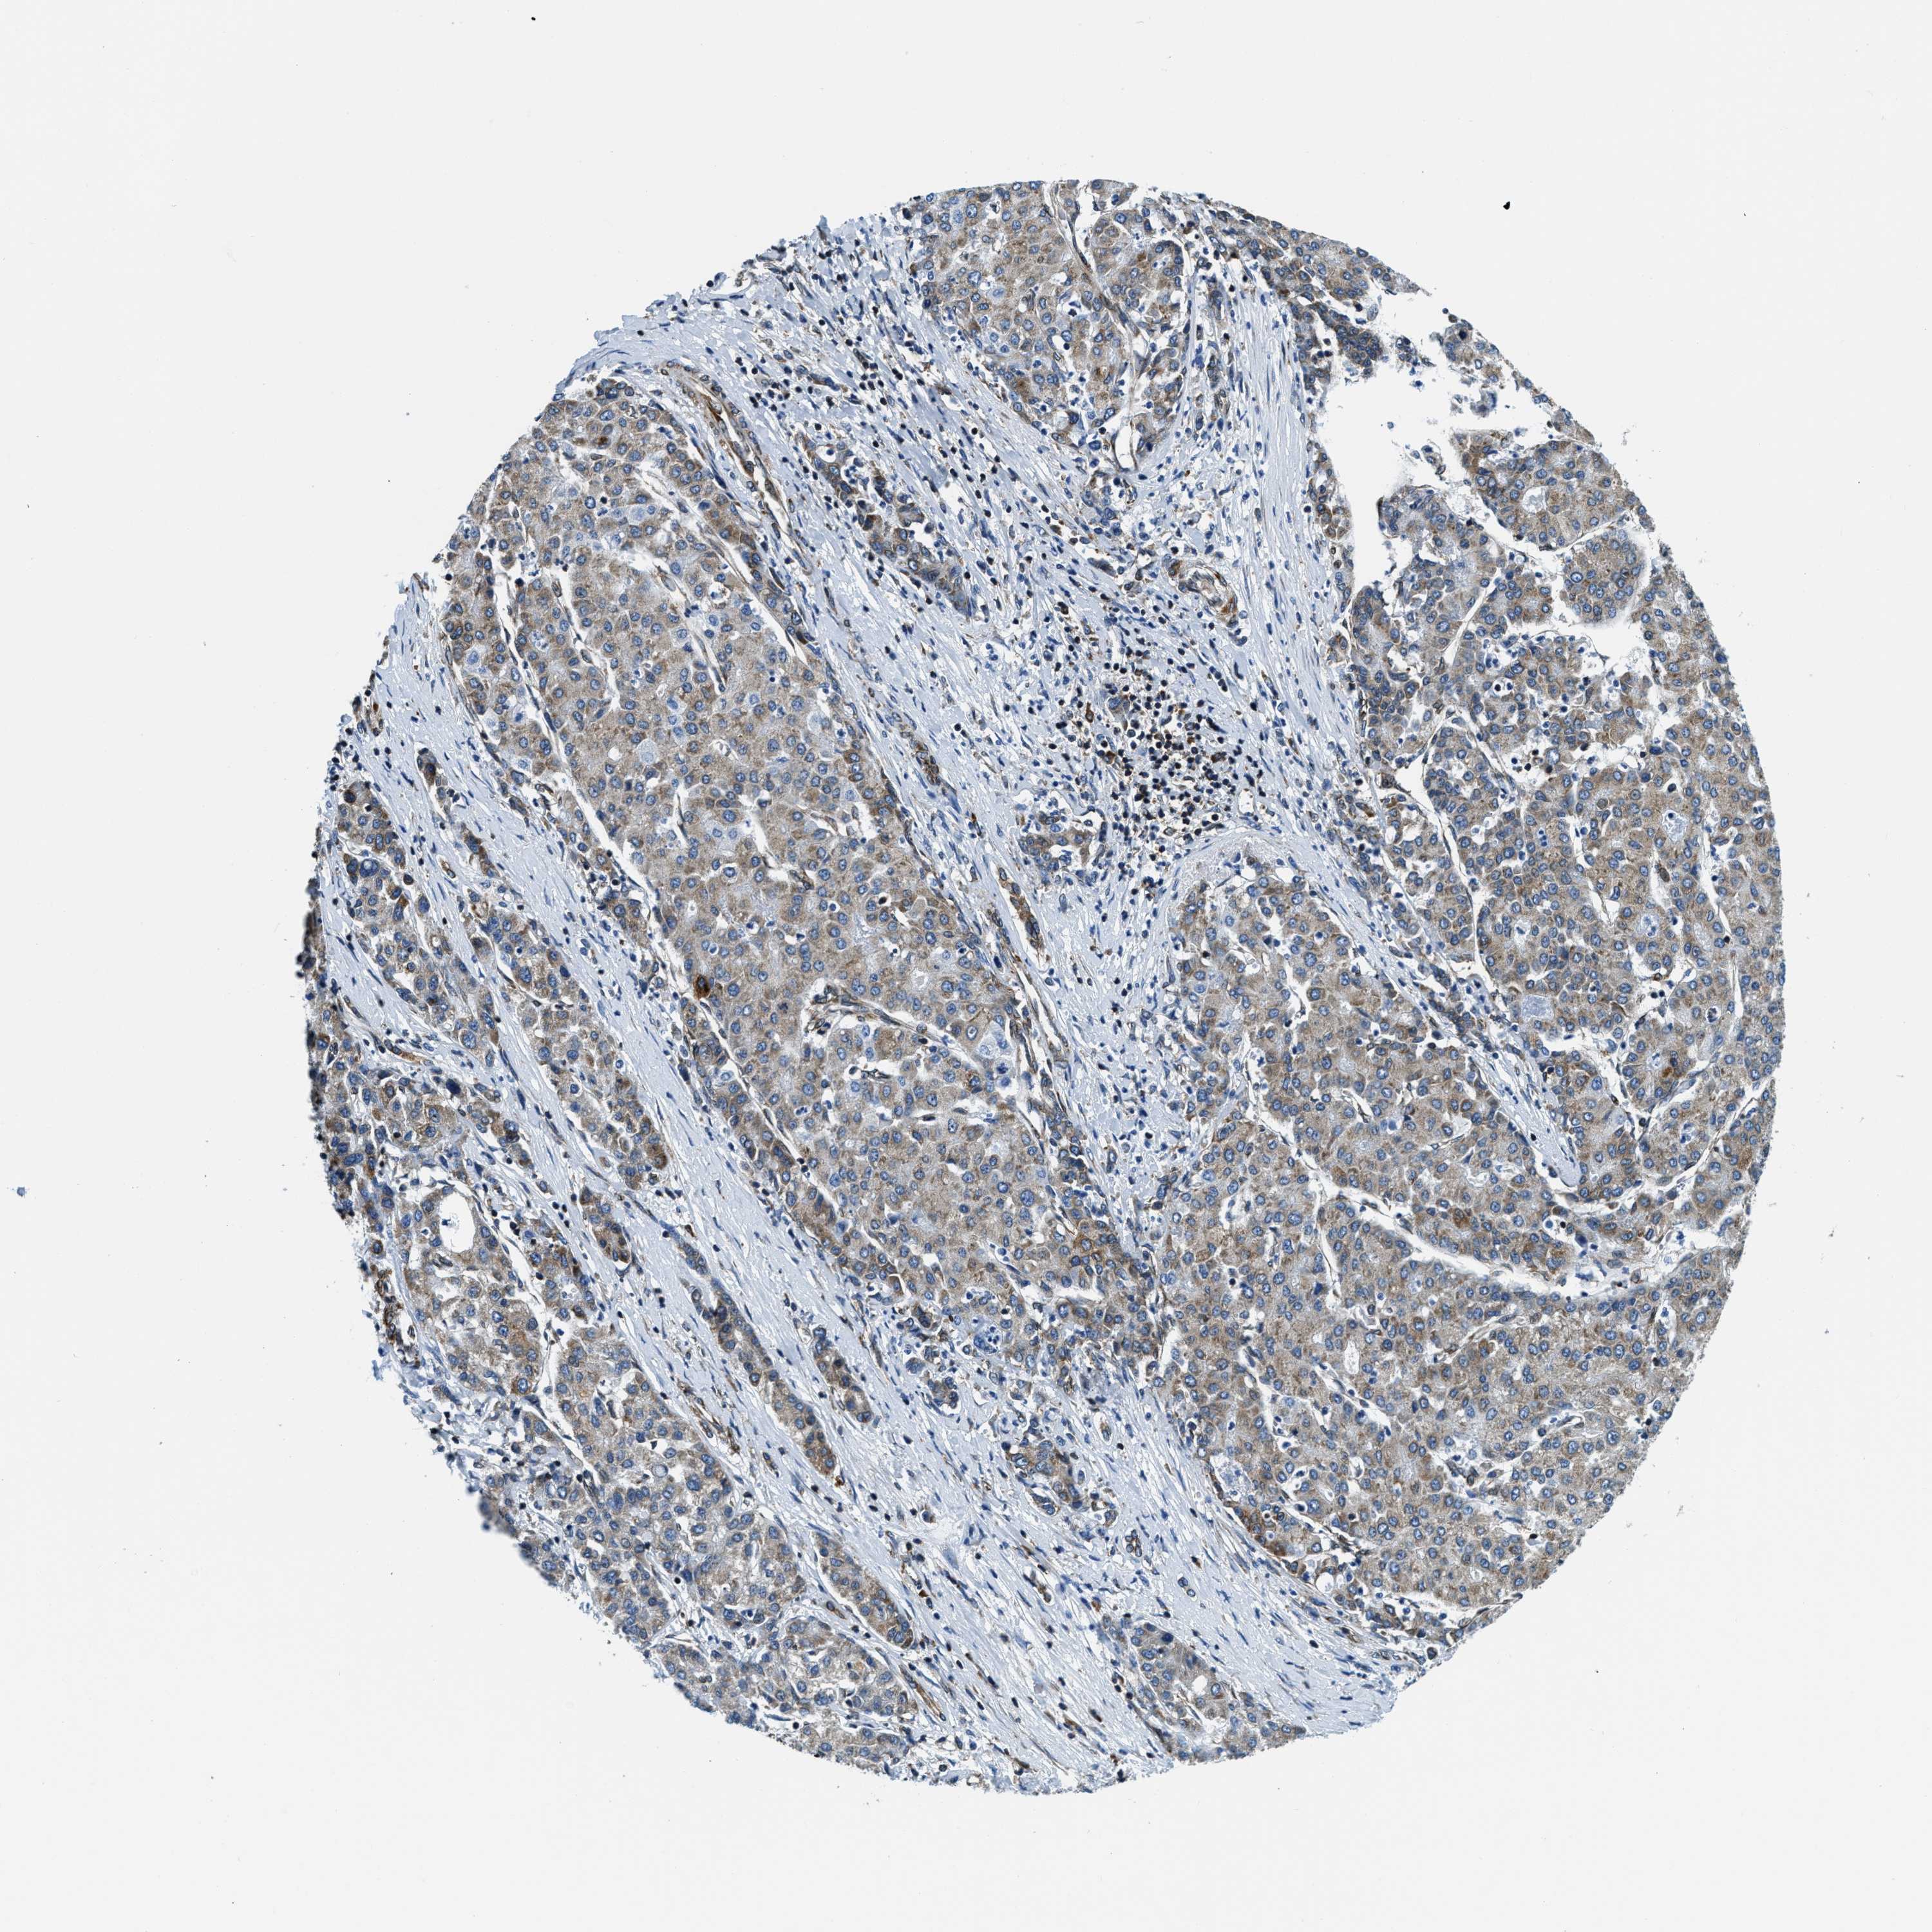

LIVER CANCER - Protein expressioni

A mouse-over function shows sample information and annotation data. Click on an image to view it in a full screen mode. Samples can be filtered based on level of antibody staining by selecting one or several of the following categories: high, medium, low and not detected. The assay and annotation is described here.

Antibody stainingi

Antibody staining in the annotated cell types in the current human tissue is reported as not detected, low, medium, or high, based on conventional immunohistochemistry profiling in selected tissues. This score is based on the combination of the staining intensity and fraction of stained cells.

Each image is clickable and will lead to virtual microscopy that enables deeper exploration of all samples and also displays staining intensity scores, fraction scores and subcellular localization as well as patient and tissue information for each sample.

Antibody HPA019698

Staining

High

Medium

Low

Not detected

Intensity

Strong

Moderate

Weak

Negative

Quantity

>75%

75%-25%

<25%

None

Location

Nuclear

Cytoplasmic/membranous

Cytoplasmic/membranous,nuclear

Cholangiocarcinoma

Carcinoma, Hepatocellular, NOS